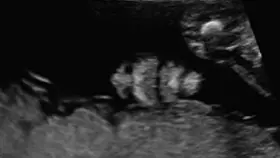

• ❤ Se realiza la evaluación estructural anatómica del feto de manera detallada, permite identificar que se hayan formado adecuadamente todos los órganos del bebé, permite detectar alteraciones o defectos estructurales.

Todas las pacientes embarazadas deben realizarse este ultrasonido entre la semana 18-24 de gestación y solo deberá ser realizado por un médico especializado y altamente capacitado, como un médico materno fetal.